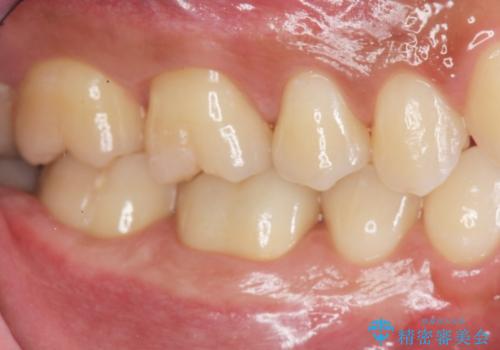

1. 放置してしまった虫歯の治療の治療前